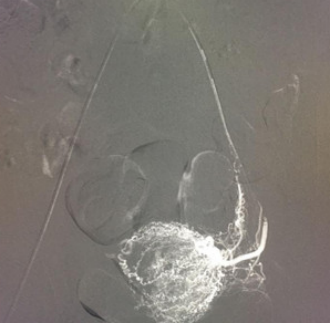

该患者孕囊位于子宫切口处肌壁内,且该处肌层菲薄,厚约3.75px(如图1,2,3)。出血风险及子宫穿孔风险极大。为了保留生育功能,确保患者生命安全,我院妇科积极发起多学科联合诊疗(MDT)会议,特邀请放射科、麻醉科、超声科等相关科室开展讨论,一致决定先由放射科行子宫动脉栓塞术并灌注甲氨蝶呤杀胚治疗(微创介入),72小时之内再行清宫术。最终,该患者在放射科顺利完成甲氨蝶呤灌注和双侧子宫动脉栓塞(如图4-5)的情况下,第二天由妇科在超声科床旁监护下成功完成清宫术(如图6),宫腔镜检查宫腔及切口处无异常。术中出血仅有5ml(出血量较常规清宫术明显减少),并于术后第三天康复出院。

图4:子宫动脉造影,血管迂曲,血供丰富,染色深浓。

image.png

图5:子宫动脉栓塞后造影,子宫动脉主干、包括支配卵巢和阴道的血管保留,子宫染色消失。

值得了解

子宫动脉栓塞术:是通过介入方法用栓塞物(如明胶海绵)将子宫动脉栓塞,以达到快速止血的作用。主要用于子宫急性大量出血时可行急诊栓塞,也用于异位妊娠出血,瘢痕子宫胎盘植入清宫术前预防出血。它作为一个有效的止血微创手术,为产科止血又提供了一个有效手段;它作为一种血管介入手术,无需开刀,损伤小,通过股动脉穿刺,超选择性插管术,将造影导管超选进入子宫动脉(如图4),再用明胶海绵栓塞子宫动脉以达到止血作用(如图5)。

由于考虑到年轻女性可能有再生育的需求,所以一般首选明胶海绵(>500um)进行栓塞。明胶海绵作为中期栓塞材料,能在30天左右自动被机体吸收再通,不会对患者子宫、卵巢的血管造成长期栓塞,不会影响患者以后的月经及再次怀孕,且原出血点经过一段时间的治疗恢复不再出血,从而达到治疗子宫瘢痕妊娠清宫出血过多和保护子宫的目的。